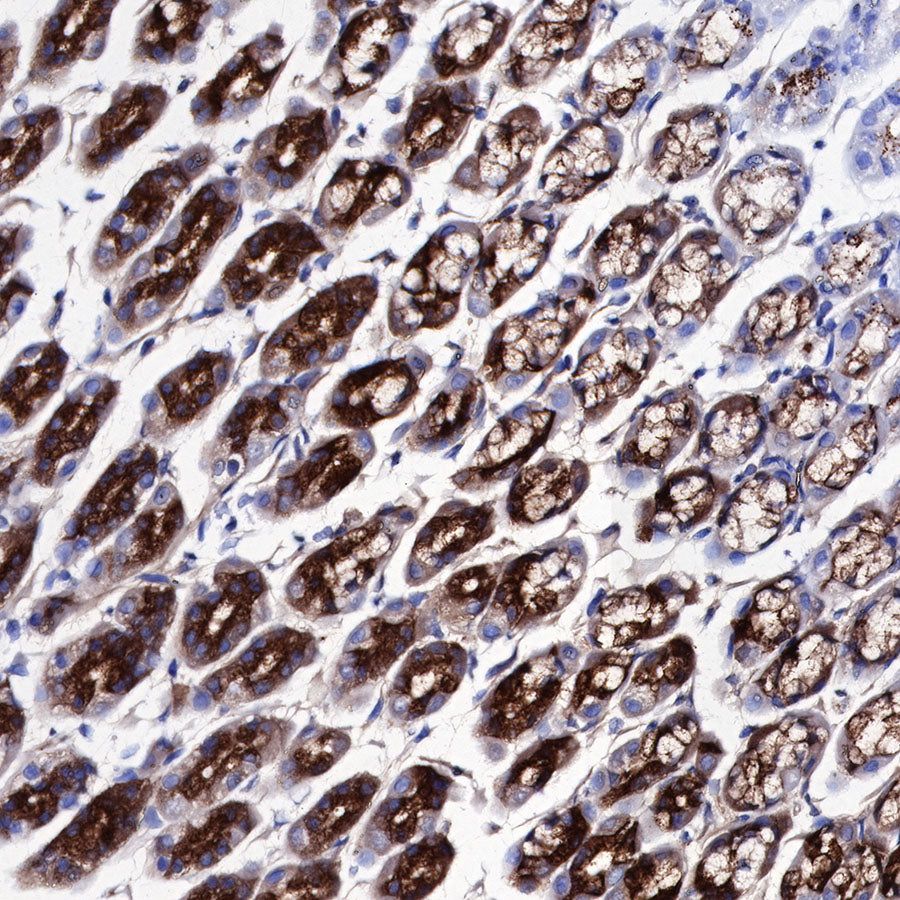

IHC shows positive staining in paraffin-embedded mouse stomach. Anti-PG II/PGC antibody was used at 1/1000 dilution, followed by a HRP Polymer for Mouse & Rabbit IgG (ready to use). Counterstained with hematoxylin. Heat mediated antigen retrieval with Tris/EDTA buffer pH9.0 was performed before commencing with IHC staining protocol.

Negative control: IHC shows negative staining in paraffin-embedded mouse liver. Anti-PG II/PGC antibody was used at 1/1000 dilution, followed by a HRP Polymer for Mouse & Rabbit IgG (ready to use). Counterstained with hematoxylin. Heat mediated antigen retrieval with Tris/EDTA buffer pH9.0 was performed before commencing with IHC staining protocol.